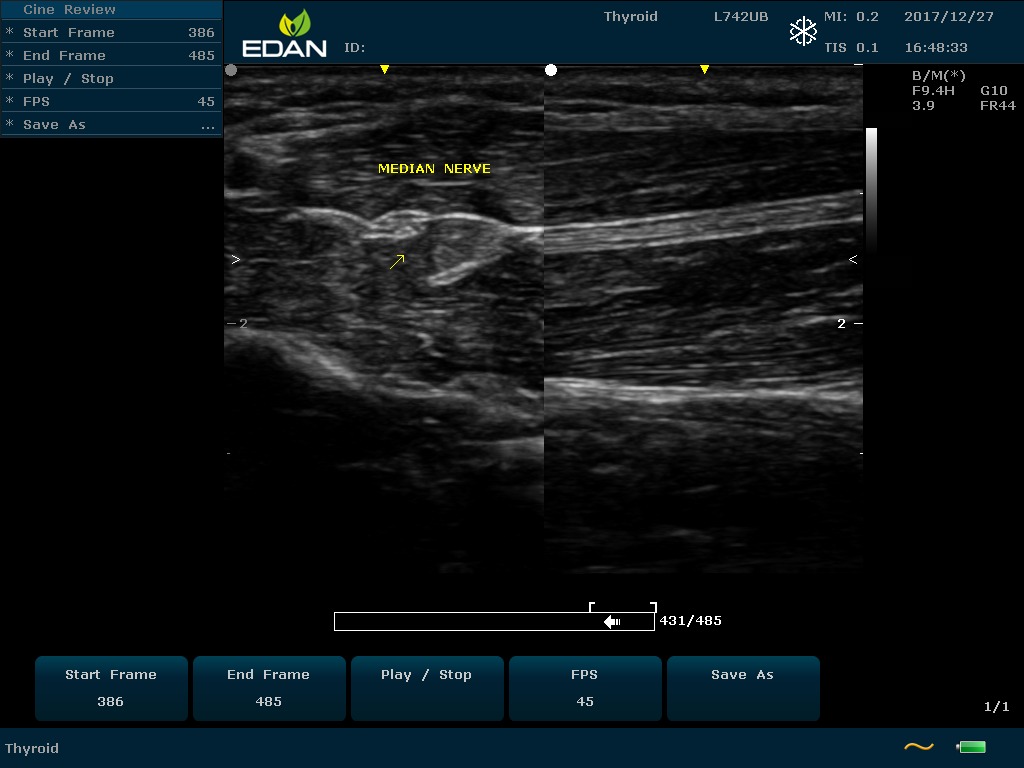

Особенность U60 Edan — расширенное применение. Ультразвуковой аппарат рекомендован для абдоминальных исследований, гинекологии и акушерства, кардиологии, педиатрии, урологии, изучения малых органов, сосудов. Для U60 Edan используются конвексные, линейные, фазированные и внутриполостные датчики.

Передовые технологии позволяют повысить качество визуализации в несколько раз. УЗИ-аппарат U60 Edan отличается возможностью быстрой настройки визуализации. Специальные функции позволяют моментально отображать данные за счет быстрой оптимизации параметров. Режимы визуализации: B-mode, M-mode, Color Doppler, Power Doppler Imaging, Pulsed Wave Doppler, Continuous Doppler.

Для улучшения качества изображений в В-режиме быстро регулируются все необходимые параметры. Быстрые инструменты изображения: LowFlow, Medium Flow, High Flow, Detail, Soft, High Contrast.